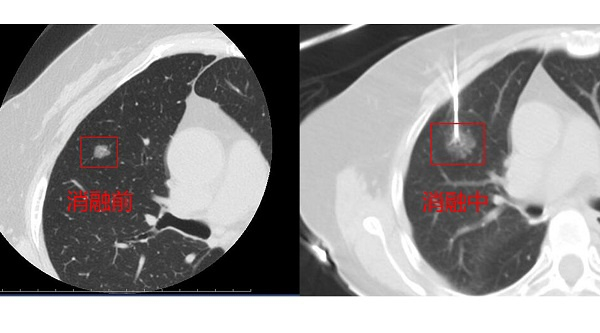

图说:上海市胸科医院“一针”射频消融,为多原发性肺癌患者解疑难 来源/采访对象提供

说起射频消融,许多人或许还有些陌生,这是一种肿瘤的介入治疗方法。治疗时,医生们运用CT引导下的三维立体重建技术,将直径不足2mm的电极针准确穿刺到患者肺部肿瘤组织中,通过电极释放的热能来“杀灭”病灶,创伤很小,恢复很快。同时,消融技术还能激发人体自身免疫系统达到消灭肿瘤细胞的作用。钟华主任介绍说:“如今临床上发现多原发性肺癌的患者越来越多,有的患者是像陈阿姨这样先后长出新病灶,更多的患者是初发现时双侧肺上就有多个病灶。外科手术很难一切再切。因此,射频消融治疗特别适用于无法耐受再次外科手术、高龄或有合并症的肺癌患者,为她们带来了救治希望。”

经过细致准备与精准定位,陈阿姨的射频治疗开始了。术中,在CT引导下,医生手中的“消融针”按照既定路线“穿行”,快速、准确地到达病灶部位,进行了精准地消融,新发的肿瘤细胞一下子就被超高温成功灭活了!由于几乎没有创伤,陈阿姨恢复得很好,术后第二天就出院了。